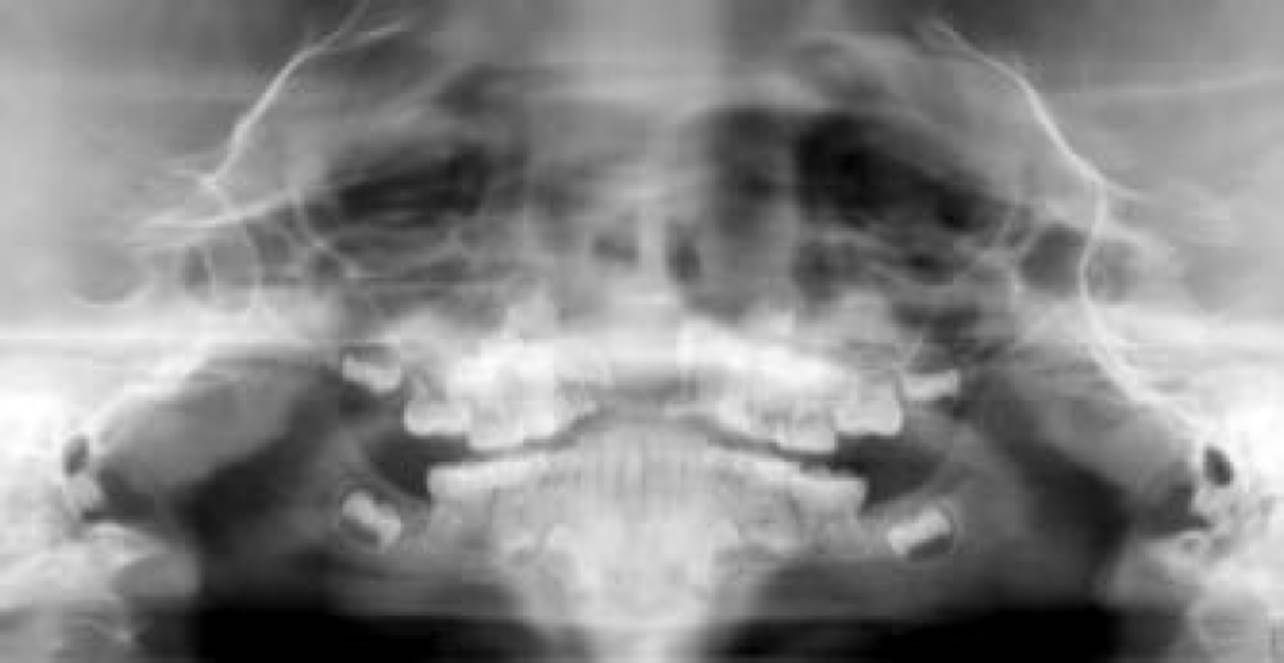

Radiográficamente, se observó un área unilocular amplia (Figura 3) que causaba desplazamiento dentario y de los gérmenes de incisivos centrales permanentes por su extensión hacia el piso de la cavidad nasal. La imagen computarizada Cone Beam permitió ver la presencia de una masa de 25 mm en la mayoría de sus dimensiones (Figura 4).

Figura 3 La ortopantomografía muestra una lesión osteolítica unilocular, con desplazamientos de órganos dentarios y gérmenes de dientes permanentes.